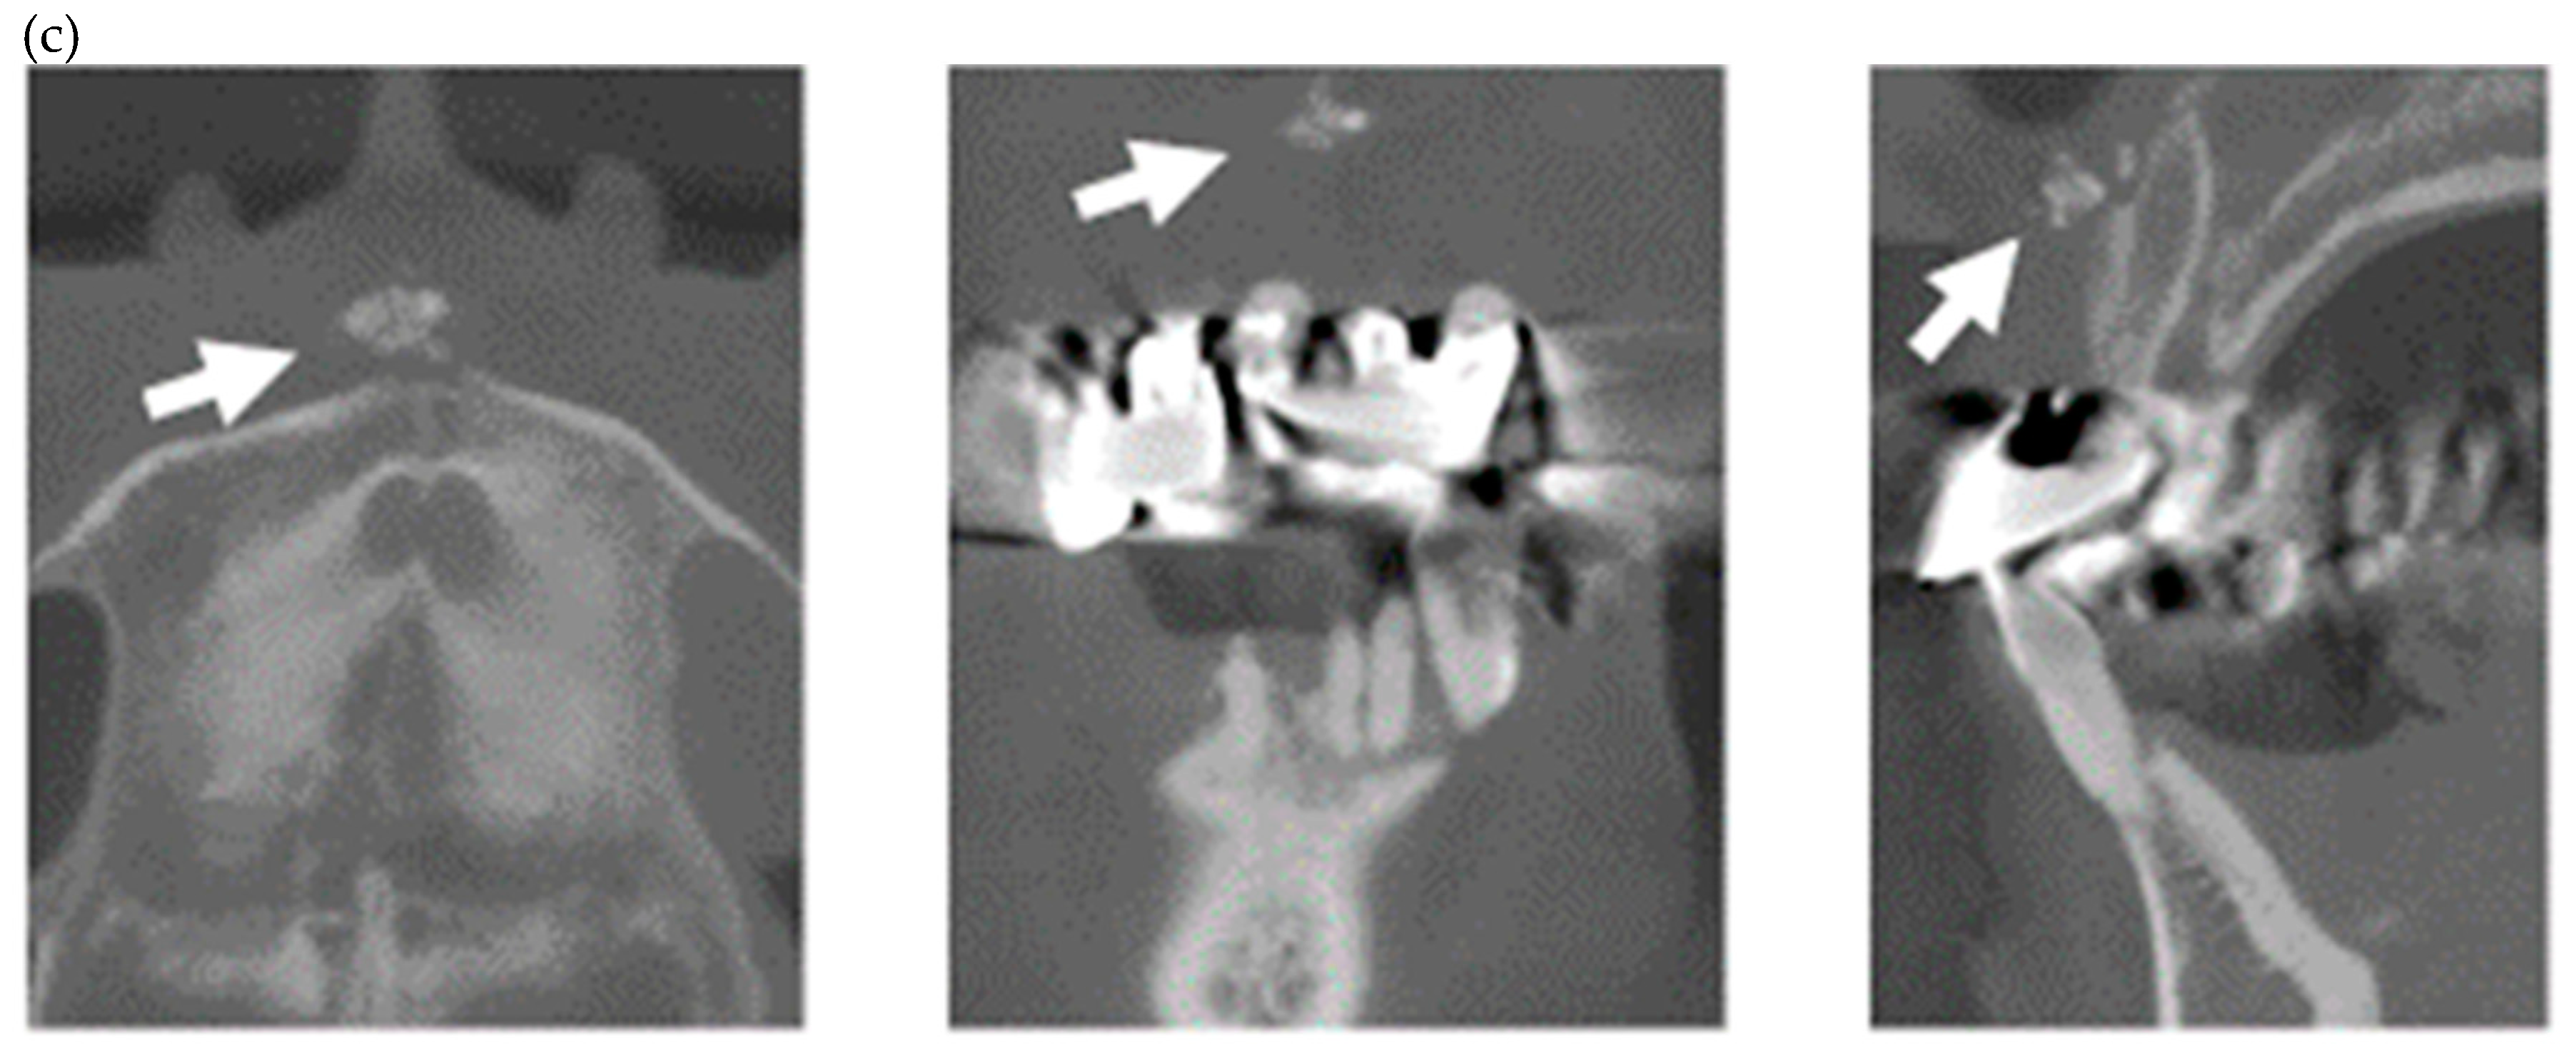

| 3 | F | 23 | dc | Y | Y | Y | Y | N | Y | N | Y | Y | Y | / | / | / | Y | Y | Y | Y | Y | Y | Y | ANA/Scl-70/SS-A | Orthodontic treatment |

| 4 | F | 11 | dc | Y | Y | Y | Y | Y | N | N | N | N | Y | / | / | / | Y | Y | Y | N | N | Y | Y | ANA/Scl-70 | calcification in PDL space/Orthodontic treatment |